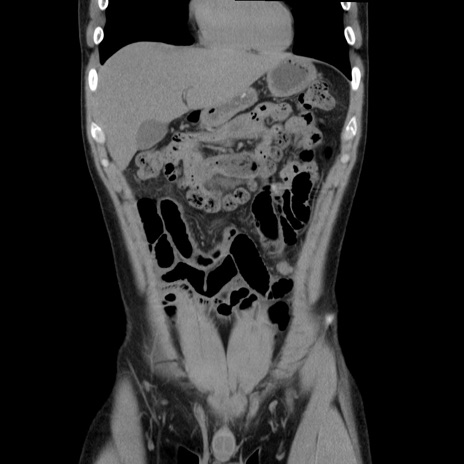

症例36(冠状断像)

【症例】20歳代 男性

【主訴】心窩部痛

【現病歴】今朝より上腹部痛あり。一旦軽快していたが再度出現したため救急要請。昨日夕に白身の魚を含む刺身を食べた。

【身体所見】BP 136/89mmHg、HR 74/min、BT 37.0℃、腹部:膨満、軟、心窩部に圧痛あり。反跳痛なし、筋性防御なし、腸雑音やや亢進あり。

【データ】WBC 17700、CRP 0.48